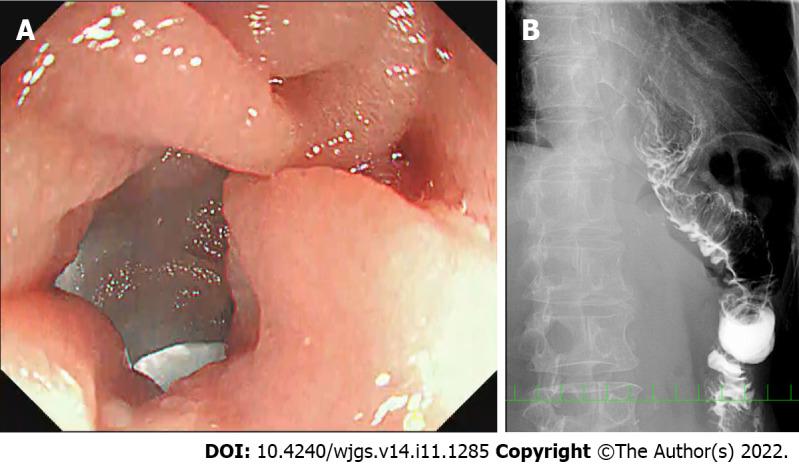

In this paper, we report unusual patients who manifested jejunal limb stricture near the esophageal hiatus without anastomotic stenosis during long-term observation after surgery.

Five patients (2.4%) had unusual jejunal limb stricture after LTG and OEJ, occurring at a mean of 10 mo after initial radical LTG. All five patients had disturbed oral intake and marked weight loss, and two had aspiration pneumonia. Various diagnostic modalities and intraoperative findings in each patient revealed an intact anastomosis, bent or tortuous jejunal limb resulting from loose fibrous adhesions on the left crus at the esophageal hiatus and no cancer recurrence. All five patients were successfully treated by reoperation for adhesiolysis, division of the left crus and rearrangement of the jejunal limb.

CONCLUSION

Disturbed passage through the jejunal limb near the hiatus can occur after some types of OEJ following LTG. We speculate that it may result from a short remnant esophagus, excessive mobilization of the jejunal limb that permits bending or tortuosity and adhesions on the left crus at the hiatus. Prevention for this complication is possible during the original LTG procedure.